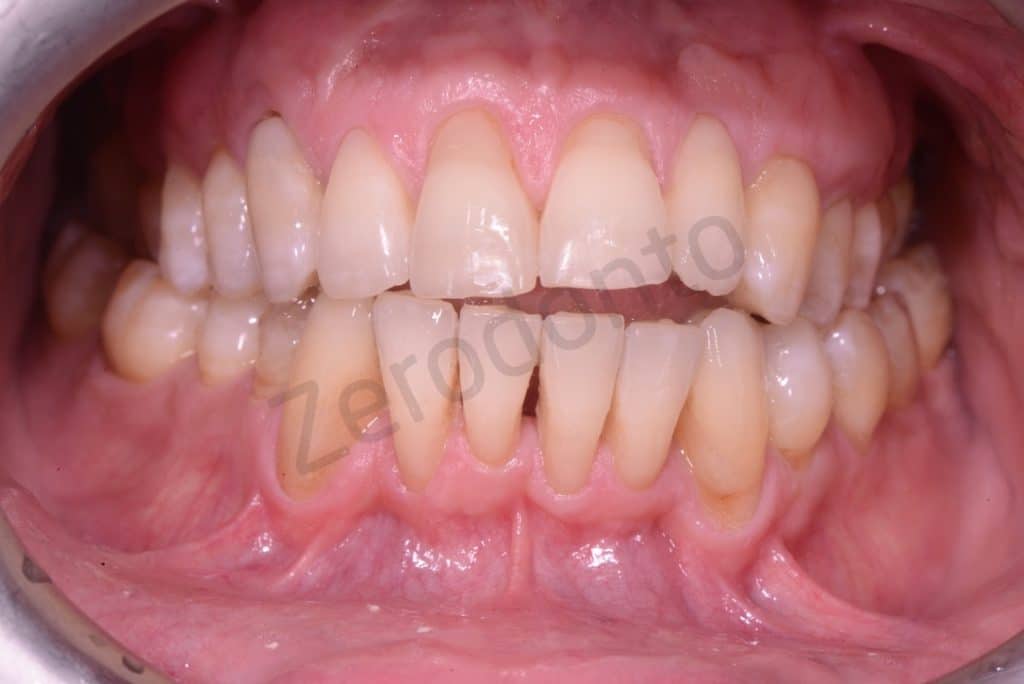

Initial situation

Frontal view